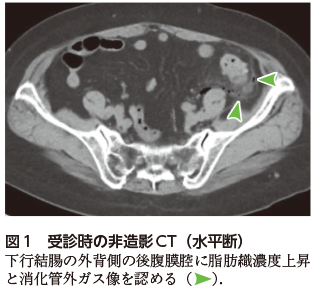

消化管穿孔/穿通および魚骨の診断にはCTが有用である.消化管穿孔/穿通の直接所見は消化管壁の不連続性であるが,穴が小さい場合は指摘が難しく,消化管外ガス像(間接所見)を契機に診断される場合が多い(図1).多量の消化管外ガス像を伴う症例は診断が容易であるが,微量のガス像のみを認める場合は見逃す恐れがある.ガスの分布は穿孔部位の推測に役立ち,後腹膜腔に広がるガスであれば十二指腸,上行結腸,下行結腸,直腸が原因として考えられる.なお,小腸穿孔,上行結腸穿孔は消化管外ガスの量が少ないことが知られている2)

図1